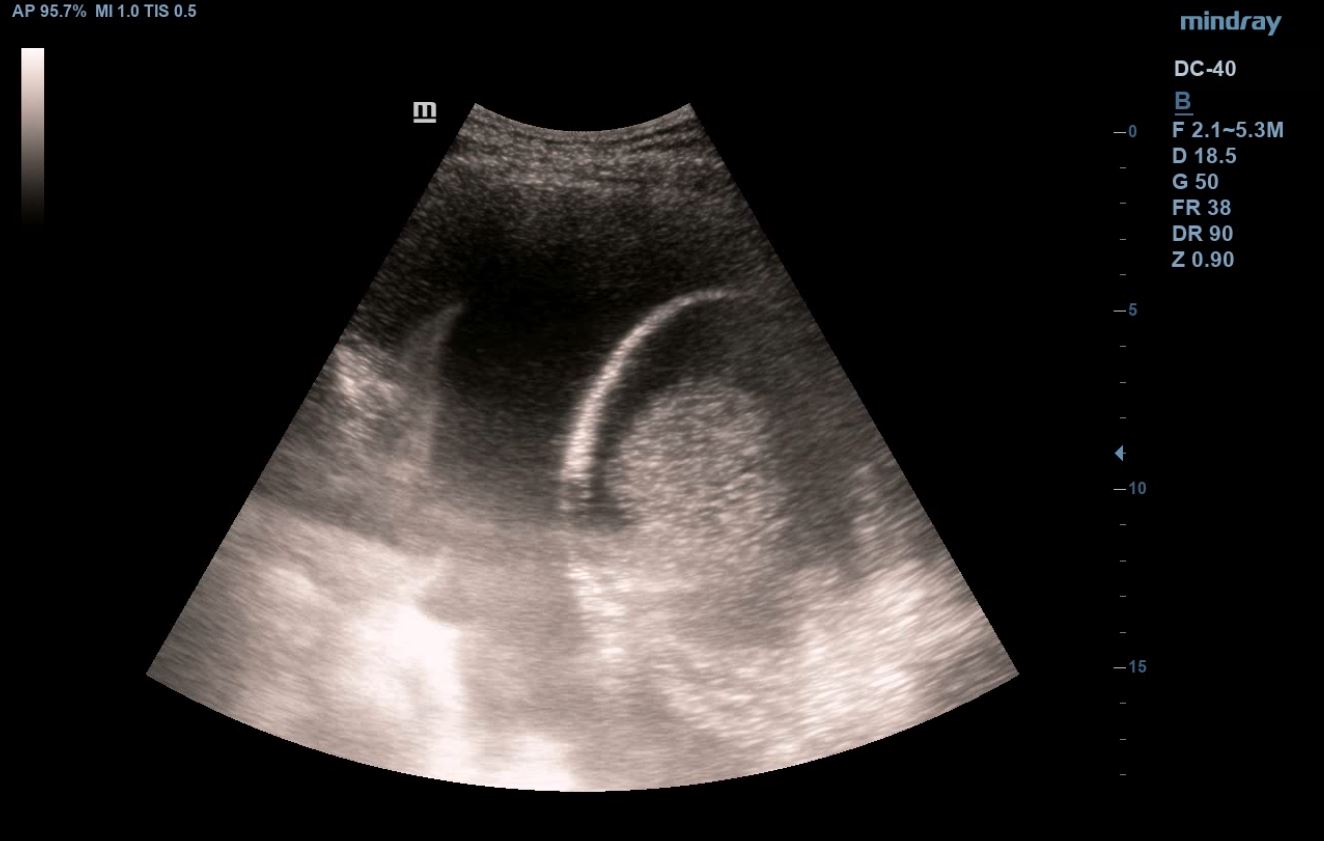

Se realiza ecografía clínica abdominal y pulmonar en la consulta, donde se visualiza líquido libre en espacio hepatorenal, esplenorenal y espacio de Douglas. En región pélvica presenta masa de aspecto heterogéneo con zonas anecoicas de 12 x 10 cm, con mapa color positivo. En la ecografía pulmonar presenta derrame pleural derecho.

En TAC toraco-abdomino-pélvico se describe «Gran masa pélvica de densidad heterogénea de 12 x 21 x 18 cm que sugiere neoplasia de origen ginecológico como primera posibilidad. Abundante líquido libre abdominal y pleural bilateral».